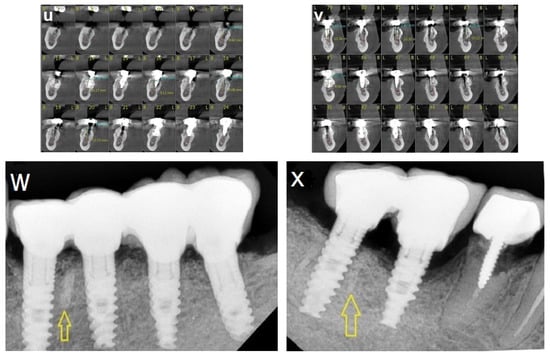

2.5.2. Case 2 (Patient No. 12)

A 47-year-old healthy female patient was referred to our clinic for bilateral augmentation of the posterior mandible and dental implant placement. She was treated using the honeycomb technique and underwent bilateral augmentation of the posterior mandibular ridges. Figure 7 presents the CBCT scans before and after the augmentation procedure (Figure 7a–f), as well as the stable outcomes observed after 13 years of follow-up (Figure 7g,h).

Figure 7.

(a–c) CBCT scan images reveal severe horizontal atrophy in the molar regions bilaterally. (d–f) CBCT scan images taken after honeycomb bone grafting demonstrate significant bone gain. (g); Implants, (h,i) images taken 13-year follow-up after implant loading.